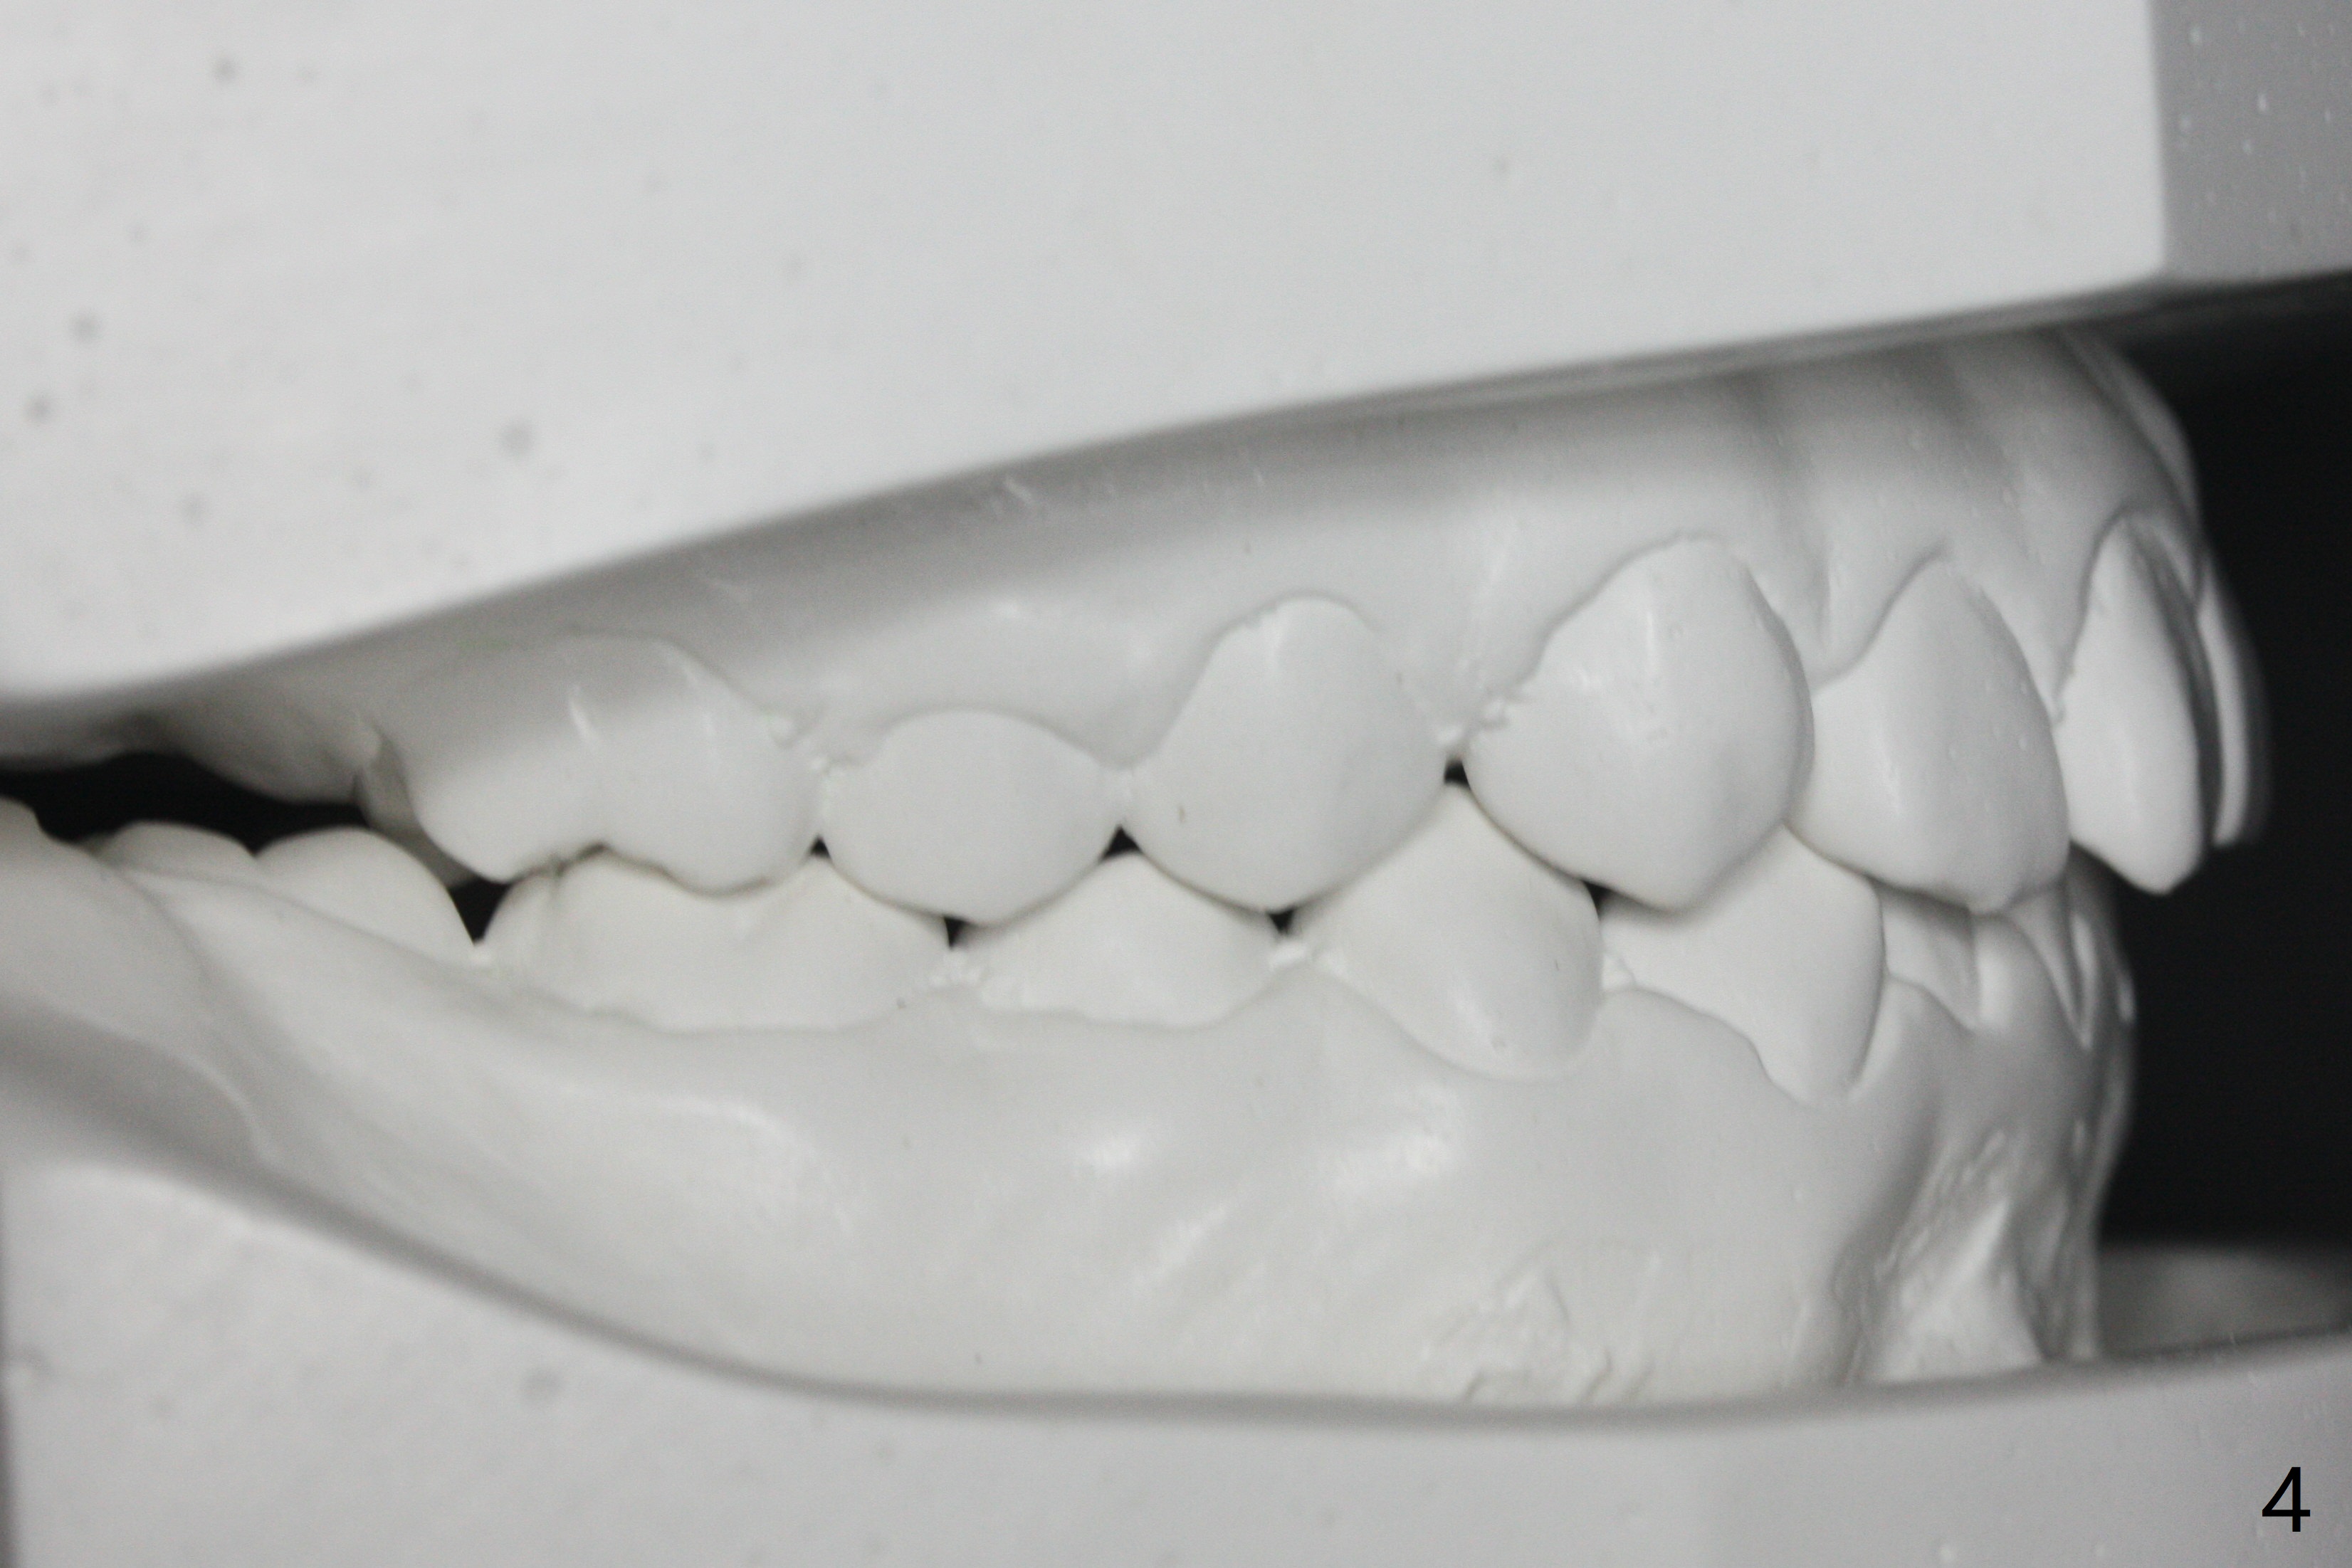

| Pre-op (11 y/o) | Post-op (12 y/o) | Follow Up (14 y/o) |

A 11-year-old man starts orthodontic treatment and finishes in 9 months. Two years later crowding relapses because of loss of suck down retainers. It appears that lingual retainer is necessary.